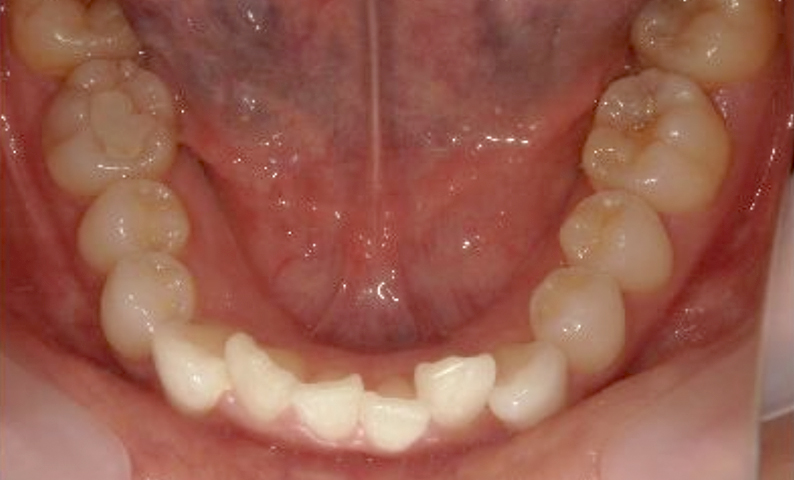

症例_025 上下顎の部分矯正

治療期間:13ヶ月金額:51万円+税女性前歯のガタガタ出っ歯

| Before | After |

|---|---|